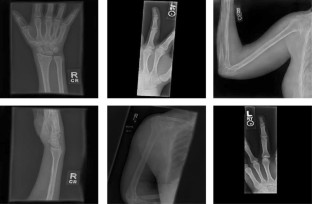

Fig. 2

Fig. 3

Fig. 4

Fig. 5

Fig. 6

Fig. 7